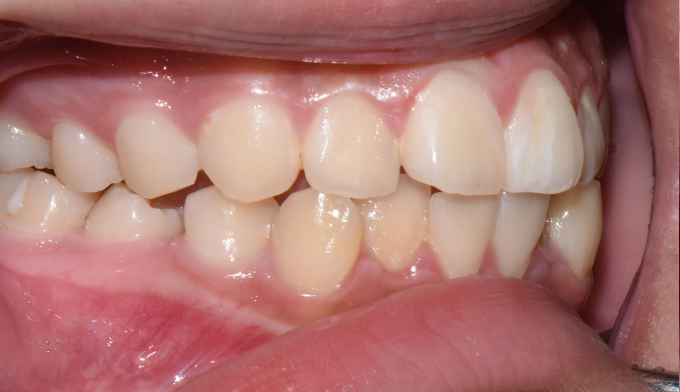

앞니불규칙

Before

After